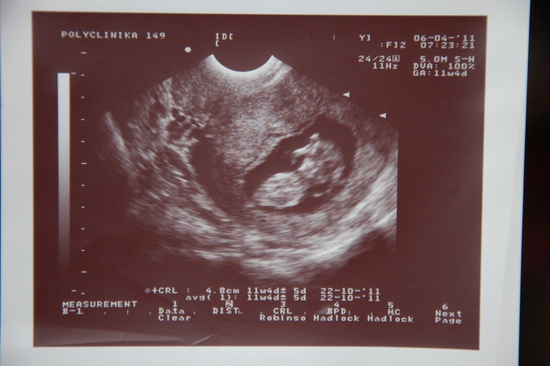

Малипууусечка в анфас:)

Нам тут 12 неделек и 4 дня :) Умываемся и машем маме ручками))))))

Поздравляю, счачтье то какое, я тоже была сегодня на УЗИ, такаяж фотка, и срок почти одинаковый, 12нед. 3 дня, поздравляю)))